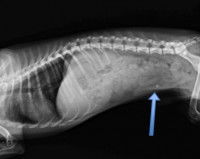

Le vétérinaire commence généralement l’examen du chien par une palpation de l’abdomen, et confirme le diagnostic d’occlusion intestinale par des examens complémentaires d’imagerie (le plus souvent, une radiographie ou une échographie). Dans certains cas, une prise de sang du chien permet de vérifier son état de santé général et les éventuelles conséquences de l’occlusion intestinale.